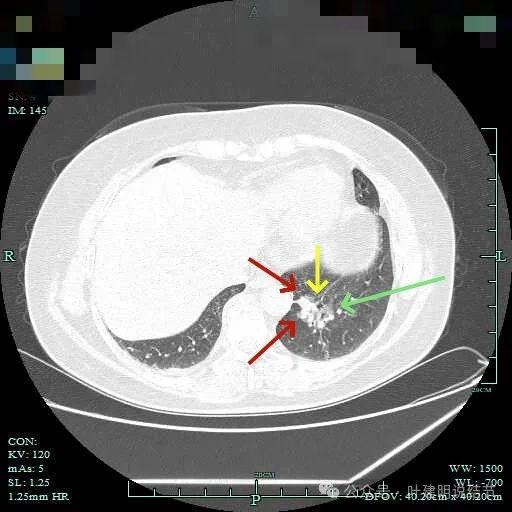

边缘略显糊,与膈肌贴着。

远侧端有阻塞性炎症的表现,病灶在些层也是磨玻璃密度。

边缘区域略显轮廓不清。